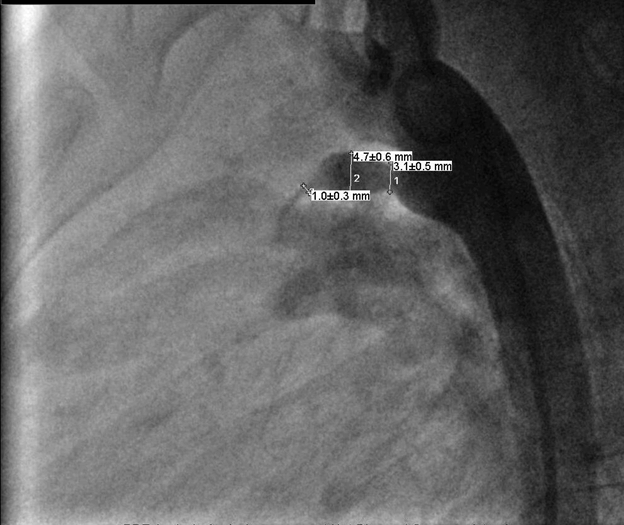

Surgery was performed after nearly one month from catheterization, under general anesthesia and median sternotomy, cardiopulmonary by-pass without cardioplegia or circulatory arrest. Aneurysm found at the pulmonary end, simple ligation with non-absorbable suture material then aneurysmorrhaphy done at both pulmonary and aortic end with a pericardial pledged, smooth postoperative period without any complication. Immediate postoperative echocardiography showed trivial shunt across the PDA but with a week later no shunt was seen across the PDA anymore (Figure 4).

Figure 4: Ligation of the patent ductus arteriosus with aortic and pulmonary side aneurysmorrhaphy.